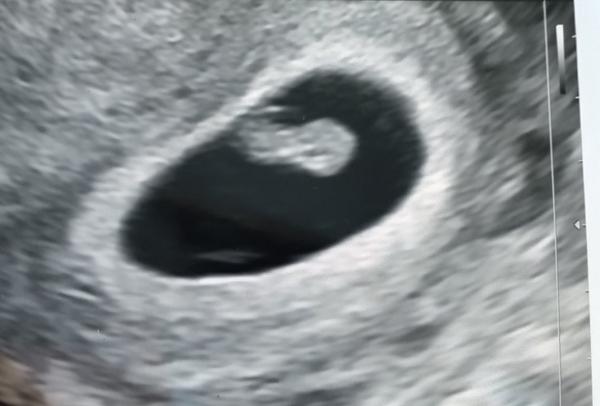

Zjisti víc o svém těhotenství: Těhotenství týden po týdnu. Neznáš týden těhotenství? Vypočítej si ho v Těhotenské kalkulačce.